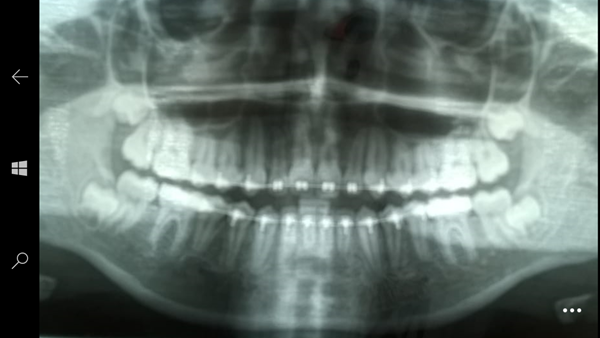

Tengo una hija de 14 años con un tratamiento de ortodoncia, que ya está por terminar en unos 3-4 meses. La Dra al ver una radiografía (anexo al final) mencionó que es necesario sacarle una muela del juicio para que no vaya a "afectar el tratamiento de ortodoncia". Mi hija no tiene síntoma alguno de muelas del juicio, ni siquiera ha brotado alguna. ¿Es necesaria que se la saquen?